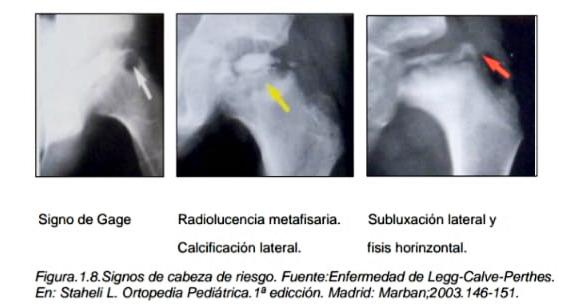

Signo de la cabeza de riesgo: Calcificación lateral de la epífisis, horizontalización fisis, subluxación lateral de la cabeza femoral, signo de Gage o zona osteolítica lateral metafisoepifisaria y radiolúcida metafisaria. Su presencia avisa sobre una evolución y deformidad epifisaria, con malos resultados y de generación articular precoz 13. Contractura en aducción y/o flexión de cadera que si son mantenidas limitan la movilidad y puede condicionar la subluxación lateral.